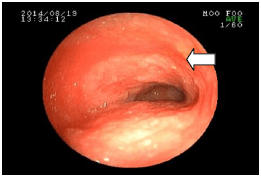

4. 胃のしこりを調べた例

![]() |

吐きを繰り返している犬の胃の中です。 ぐるりと内側を取り囲むように腫れあがっていました。(矢印) |